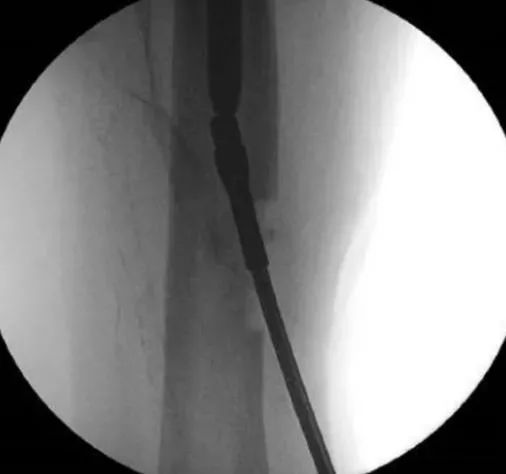

À l'aide d'un long noyau ou d'une pince laparoscopique, la partie distale peut parfois être saisie et retirée avec succès.Cependant, les pinces longues n'offrent pas une prise solide et le succès du retrait dépend du relâchement de la partie distale.

L'enfoncement d'un clou intramédullaire mince ou d'un alésoir manuel dans l'ongle cassé distal aide aussi parfois à le retirer.Pendant l'enfoncement, la goupille de verrouillage distale doit être retenue pour éviter un déplacement supplémentaire de la partie distale pendant l'enfoncement.Une fois que le clou intramédullaire mince ou l'alésoir manuel a atteint un engagement ferme avec le segment distal, retirer le clou de verrouillage distal, puis repousser pour retirer le segment distal cassé.

De nombreux rapports de la littérature sur l'utilisation d'instruments à crochet pour retirer la partie distale des ongles cassés canulés.La cavité creuse du clou intramédullaire peut être remplie de plusieurs fils de guidage en parallèle le long de la direction du crochet d'extraction pour éviter le découplage pendant le processus d'extraction.La technique de bourrage à fils guides multiples est aussi parfois une alternative aux crochets d'extraction.